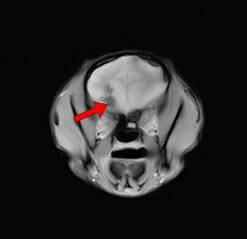

脑炎(图一) 脑炎(图二)